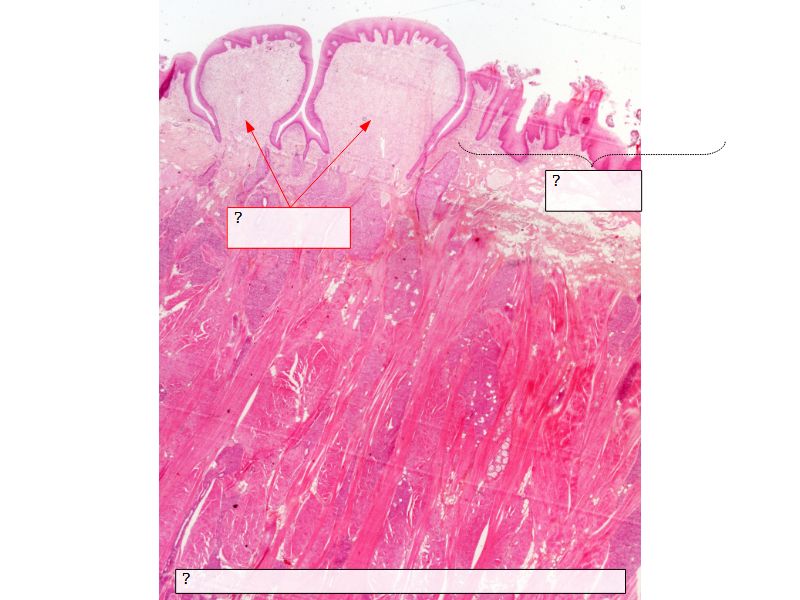

Fill in all the missing labels, and assess as you move through the slides. Answers on the down slide. It is important to do this using pen and paper, and not just glance through the images.